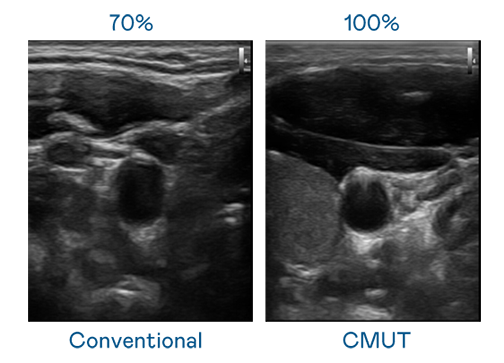

CMUT 技术是一种用电容式微机电元件来产生超音波讯号的技术。与传统 PZT 压电式技术相比,CMUT 频宽增加 30%,更宽频的超音波讯号让影像解析度大幅提升,是实现高影像品质医疗超音波扫描、促进精准医疗发展的关键技术。

大频宽带来超清晰影像

超音波影像的解析度高低,首先取决于探头能发出的讯号频宽。aoa体育 CMUT 可提供高清晰的超音波讯号,提供高频宽、高灵敏度、影像纹理细节更高的超音波影像,协助医护人员缩短影像判读时间及利用精准的医疗影像进行诊断。